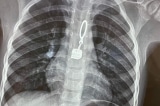

7 cây kim gỉ sét ghim trong lồng ngực một bệnh nhân

Bệnh nhân được xác định bị trầm cảm nặng, đã tự dùng kim đâm vào cơ thể.